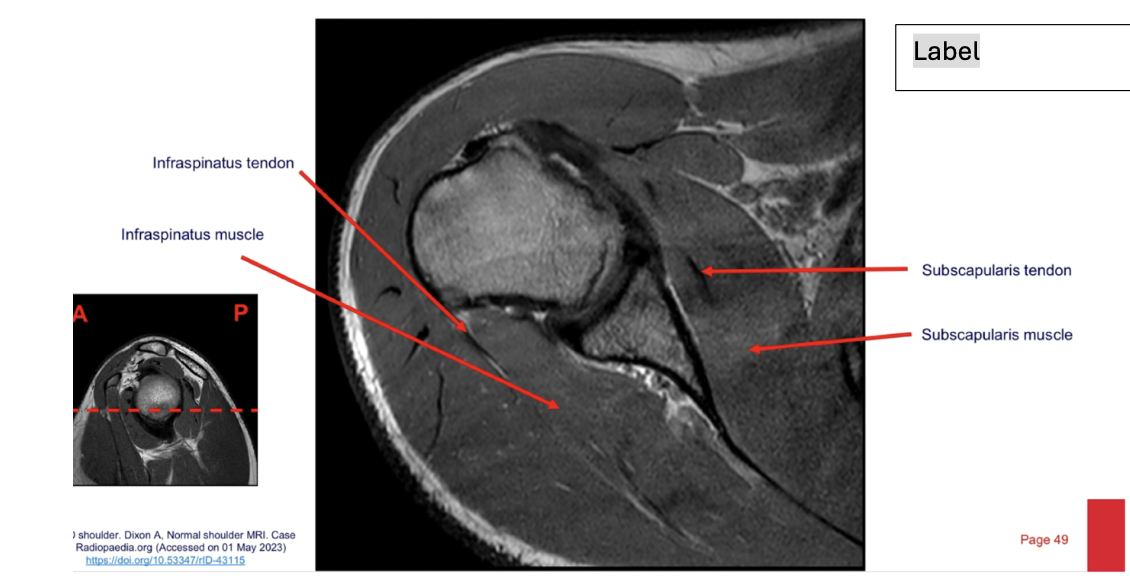

label each

2- lateral and medial condyles of femur

4- vastus lateralis muscle

5-posterior cruciate ligament

6- anterior cruciate ligament

7- medial meniscus of knee

8- lateral meniscus of knee

9-tibia

10-fibula